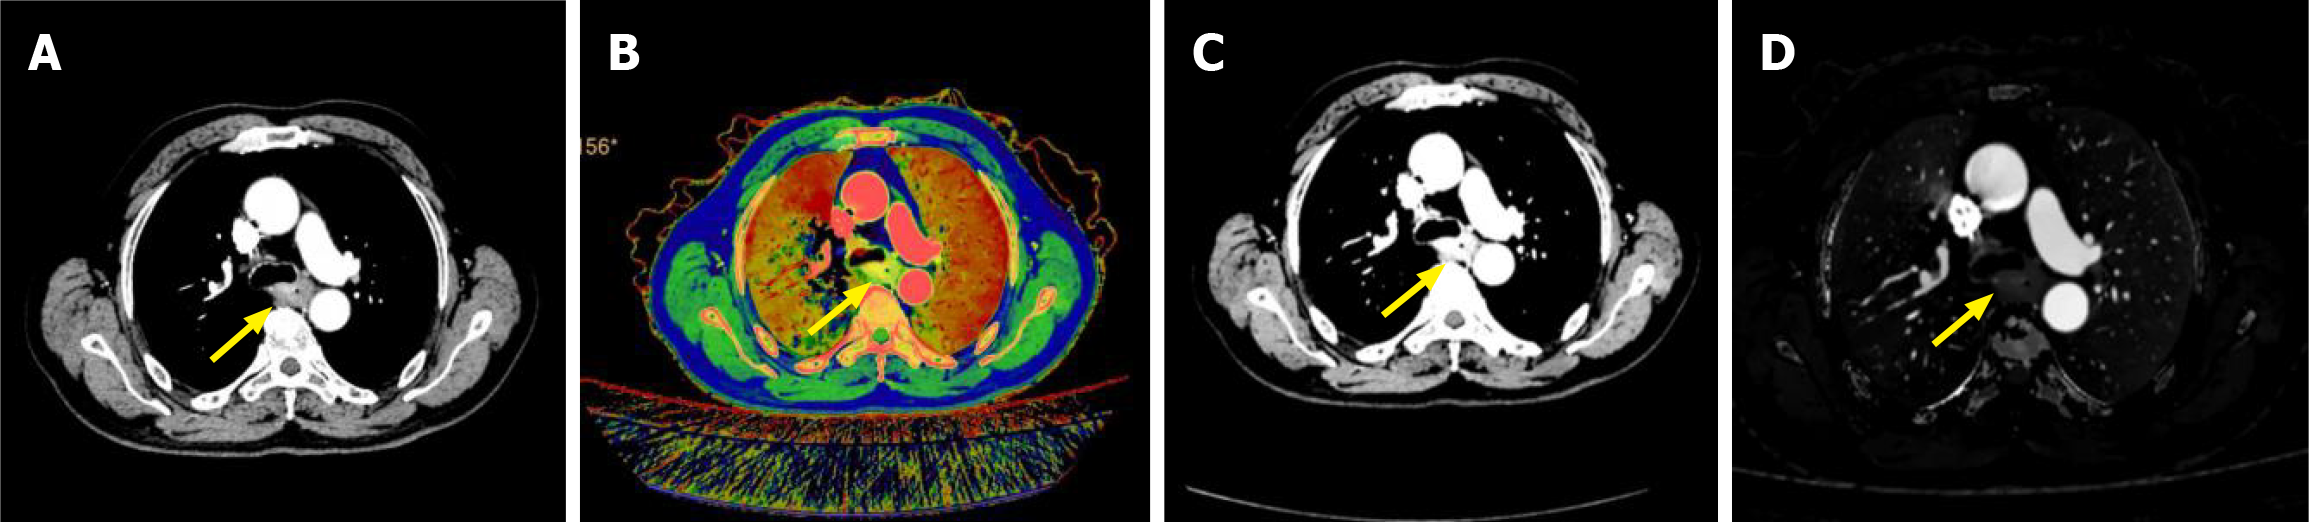

DLCT example images of a 72-year-old male EC patient are shown in Figure 1. With the advancement of radiological technology, DLCT has shown potential as a non-invasive method for predicting therapeutic efficacy in EC. With regard to proton therapy for middle-thoracic EC, the stopping power ratio (SPR) derived from DLCT has a dosimetric impact comparable to that of dose calculation based on CT-HU conversion for target coverage and organ-at-risk sparing[10]. The SPR obtained from DLCT scans may be beneficial for planning long-term or complex radiotherapy regimes. Neoadjuvant chemotherapy (NAC) has significantly improved the survival rate of patients with EC, and some drugs have been established as first-line therapy for advanced disease. However, clinical evidence reveals substantial inter-patient variability in the response to NAC. Consequently, developing a novel method for predicting the response of patients with EC to NAC is necessary. DLCT parameters are currently used primarily for assessing the prognosis of patients with EC undergoing NAC. An integrated model constructed based on DLCT-derived parameters, such as arterial enhancement fraction (AEF) and extracellular volume (ECV), and clinical parameters showed good performance in predicting pathological complete response in patients with EC undergoing NAC[11]. This model can be used as a non-invasive method for planning individualized therapeutic strategies for patients with EC. AEF is a quantitative parameter that reflects the tumor blood supply status and evaluates tumor tissue blood perfusion. ECV is a spectral imaging parameter for evaluating tissue fibrosis and alterations in matrix components. Based on the combination of these parameters, the aforementioned model provides more comprehensive information for evaluating therapeutic efficacy. Furthermore, a study reported that an independent predictor combining clinical characteristics (neutrophil-to-lymphocyte ratio and clinical stage) and VP quantitative parameters from DLCT improved the accuracy of predicting the response of patients with EC to NAC[12]. The independent predictors achieved an area under the curve (AUC) of 0.825 in the training set and 0.794 in the validation set. In a study on neoadjuvant therapy for gastroesophageal junction cancer, Graf et al[13] investigated the correlation of normalized IC (NIC) and normalized IC at diagnosis minus IC after neoadjuvant therapy (ΔIC) with tumor regression grade. The AUC value for normalized ΔIC in distinguishing responders from non-responders was 0.95, and that for post-treatment IC was 0.88. These findings suggest that ΔIC after neoadjuvant therapy is a potential imaging biomarker for treatment response. Characteristics of representative research of the clinical application of DLCT in EC depicted in Table 1. Existing studies have used spectral CT mainly for quantifying the clinical treatment response of patients with EC undergoing NAC and proton therapy, which serves as an effective indicator of therapeutic efficacy. However, no definitive conclusions have been reported regarding the application of DLCT, deep learning, and radiomic techniques in assessing molecular changes in preoperative EC tissues and predicting clinical prognosis.

Figure 1

Figure 1 Esophageal cancer and dual-layer spectral computed tomography images. A: Conventional computed tomography image in the arterial phase (AP); B: Effective atomic number in the AP; C: Virtual monochromatic image; D: Iodine concentration computed tomography in the AP.